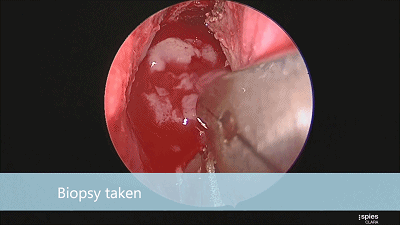

▼留取肿瘤标本。

▼本例垂体腺瘤质软,易于吸除。

▼继续仔细吸除瘤腔死角的肿瘤。